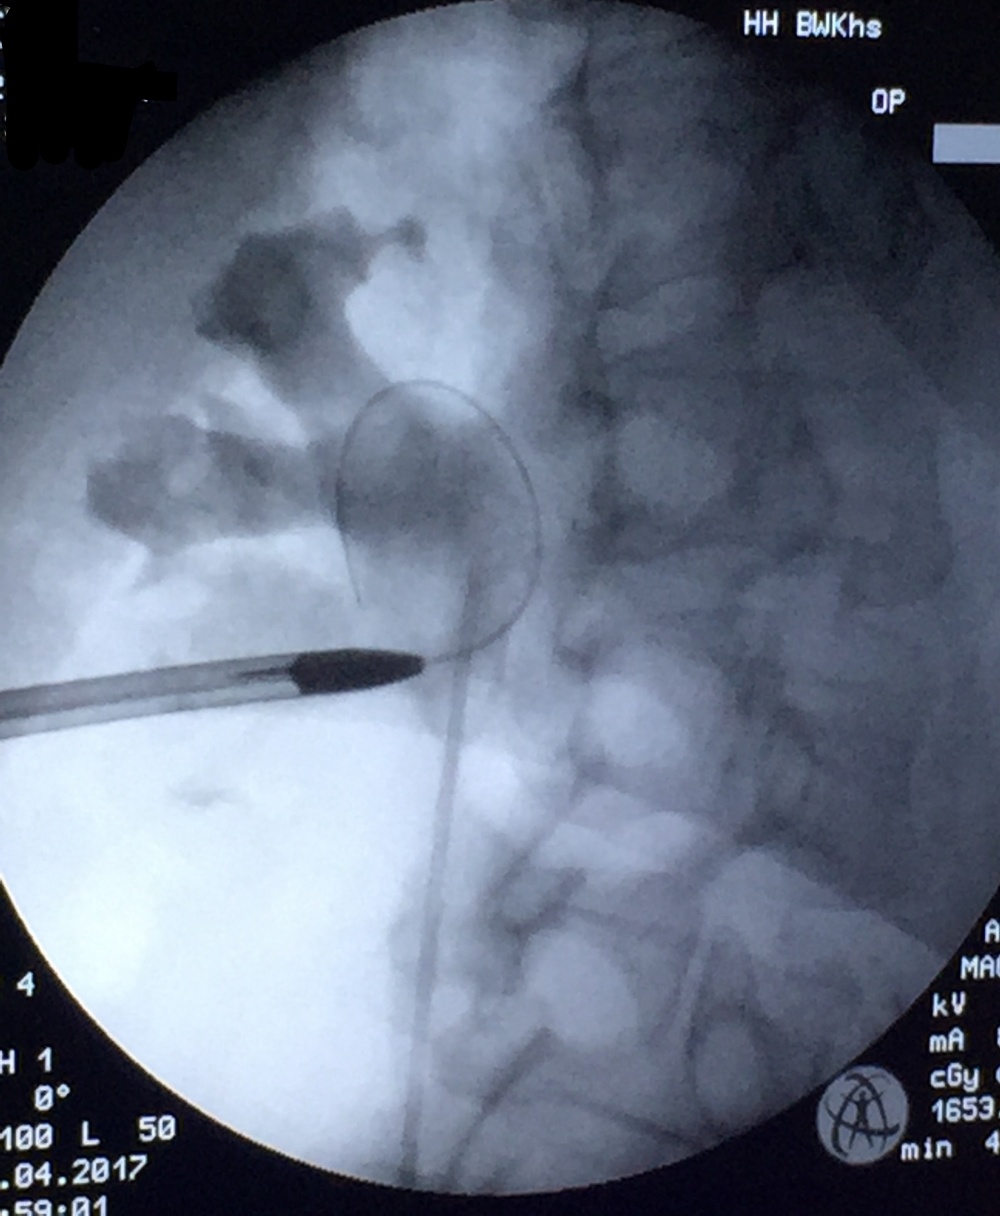

Perkutane Nephrolithotomie (PCNL)

bei der Durchführung einer PCNL.

Bei der PCNL handelt es sich um ein endoskopisches Verfahren, wobei der Zugang durch eine direkte Punktion der Niere durch die Haut erfolgt. Die Punktion wird durch Ultraschall und Röntgen gesteuert (Abbildung 8). Die Wahl der Punktionsstelle erfolgt nach dem Prinzip der besten Erreichbarkeit [16]. Im Allgemeinen wird hierbei die untere Kelchgruppe punktiert, da dort das Risiko einer Verletzung benachbarter Organe sowie auch der Stein-Haut-Abstand gering ist [6]. Durch ein Endoskop kann nach erfolgreicher Punktion die sofortige Bergung bzw. die Desintegration des Harnsteins erfolgen. Die Fragmente werden je nach Technik ausgespült (z. B. Mini-PCNL mit offenem Spülsystem), mit Körbchen geborgen oder gehen auf natürlichem Weg ab. In den meisten Fällen wird intraoperativ eine perkutane Nephrostomie oder ein DJ eingelegt, um den Harnabfluss zu gewährleisten [16, 6].